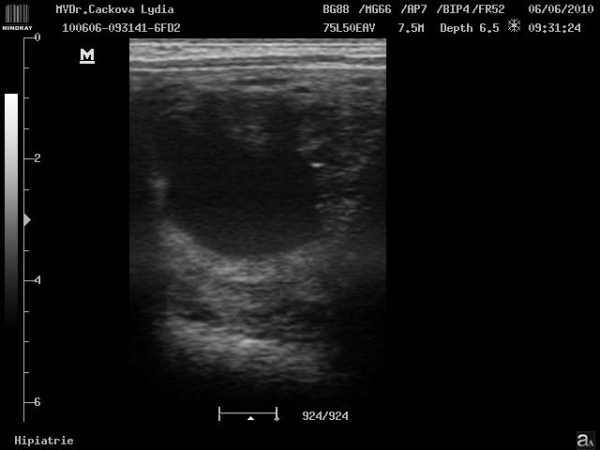

Preovulační folikul

ultrasonografické vyšetření klisny